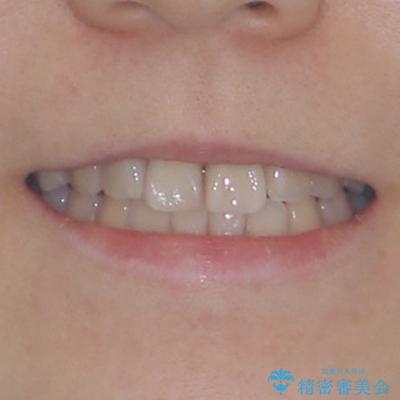

根管治療を行った歯はクラウンによる補綴治療が必要となりますが、高校生の頃に行った矯正治療の後戻りも気になるとのことで、補綴治療を行う前に矯正治療を行うこととしました。

後戻りは軽度であり、インビザラインにて歯列を整え、その後にオールセラミッククラウンにて補綴治療を行うこととしました。